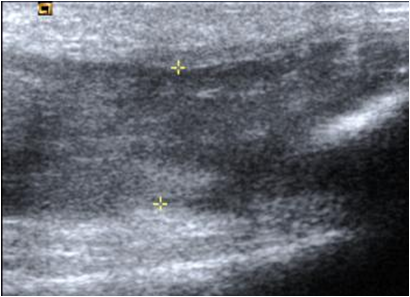

Fig 148. Tendinitis crónica.

Ecografía: Vista longitudinal del tendón patelar, el cual está engrosado y con pérdida de su patrón fibrilar, por tendinitis crónica.